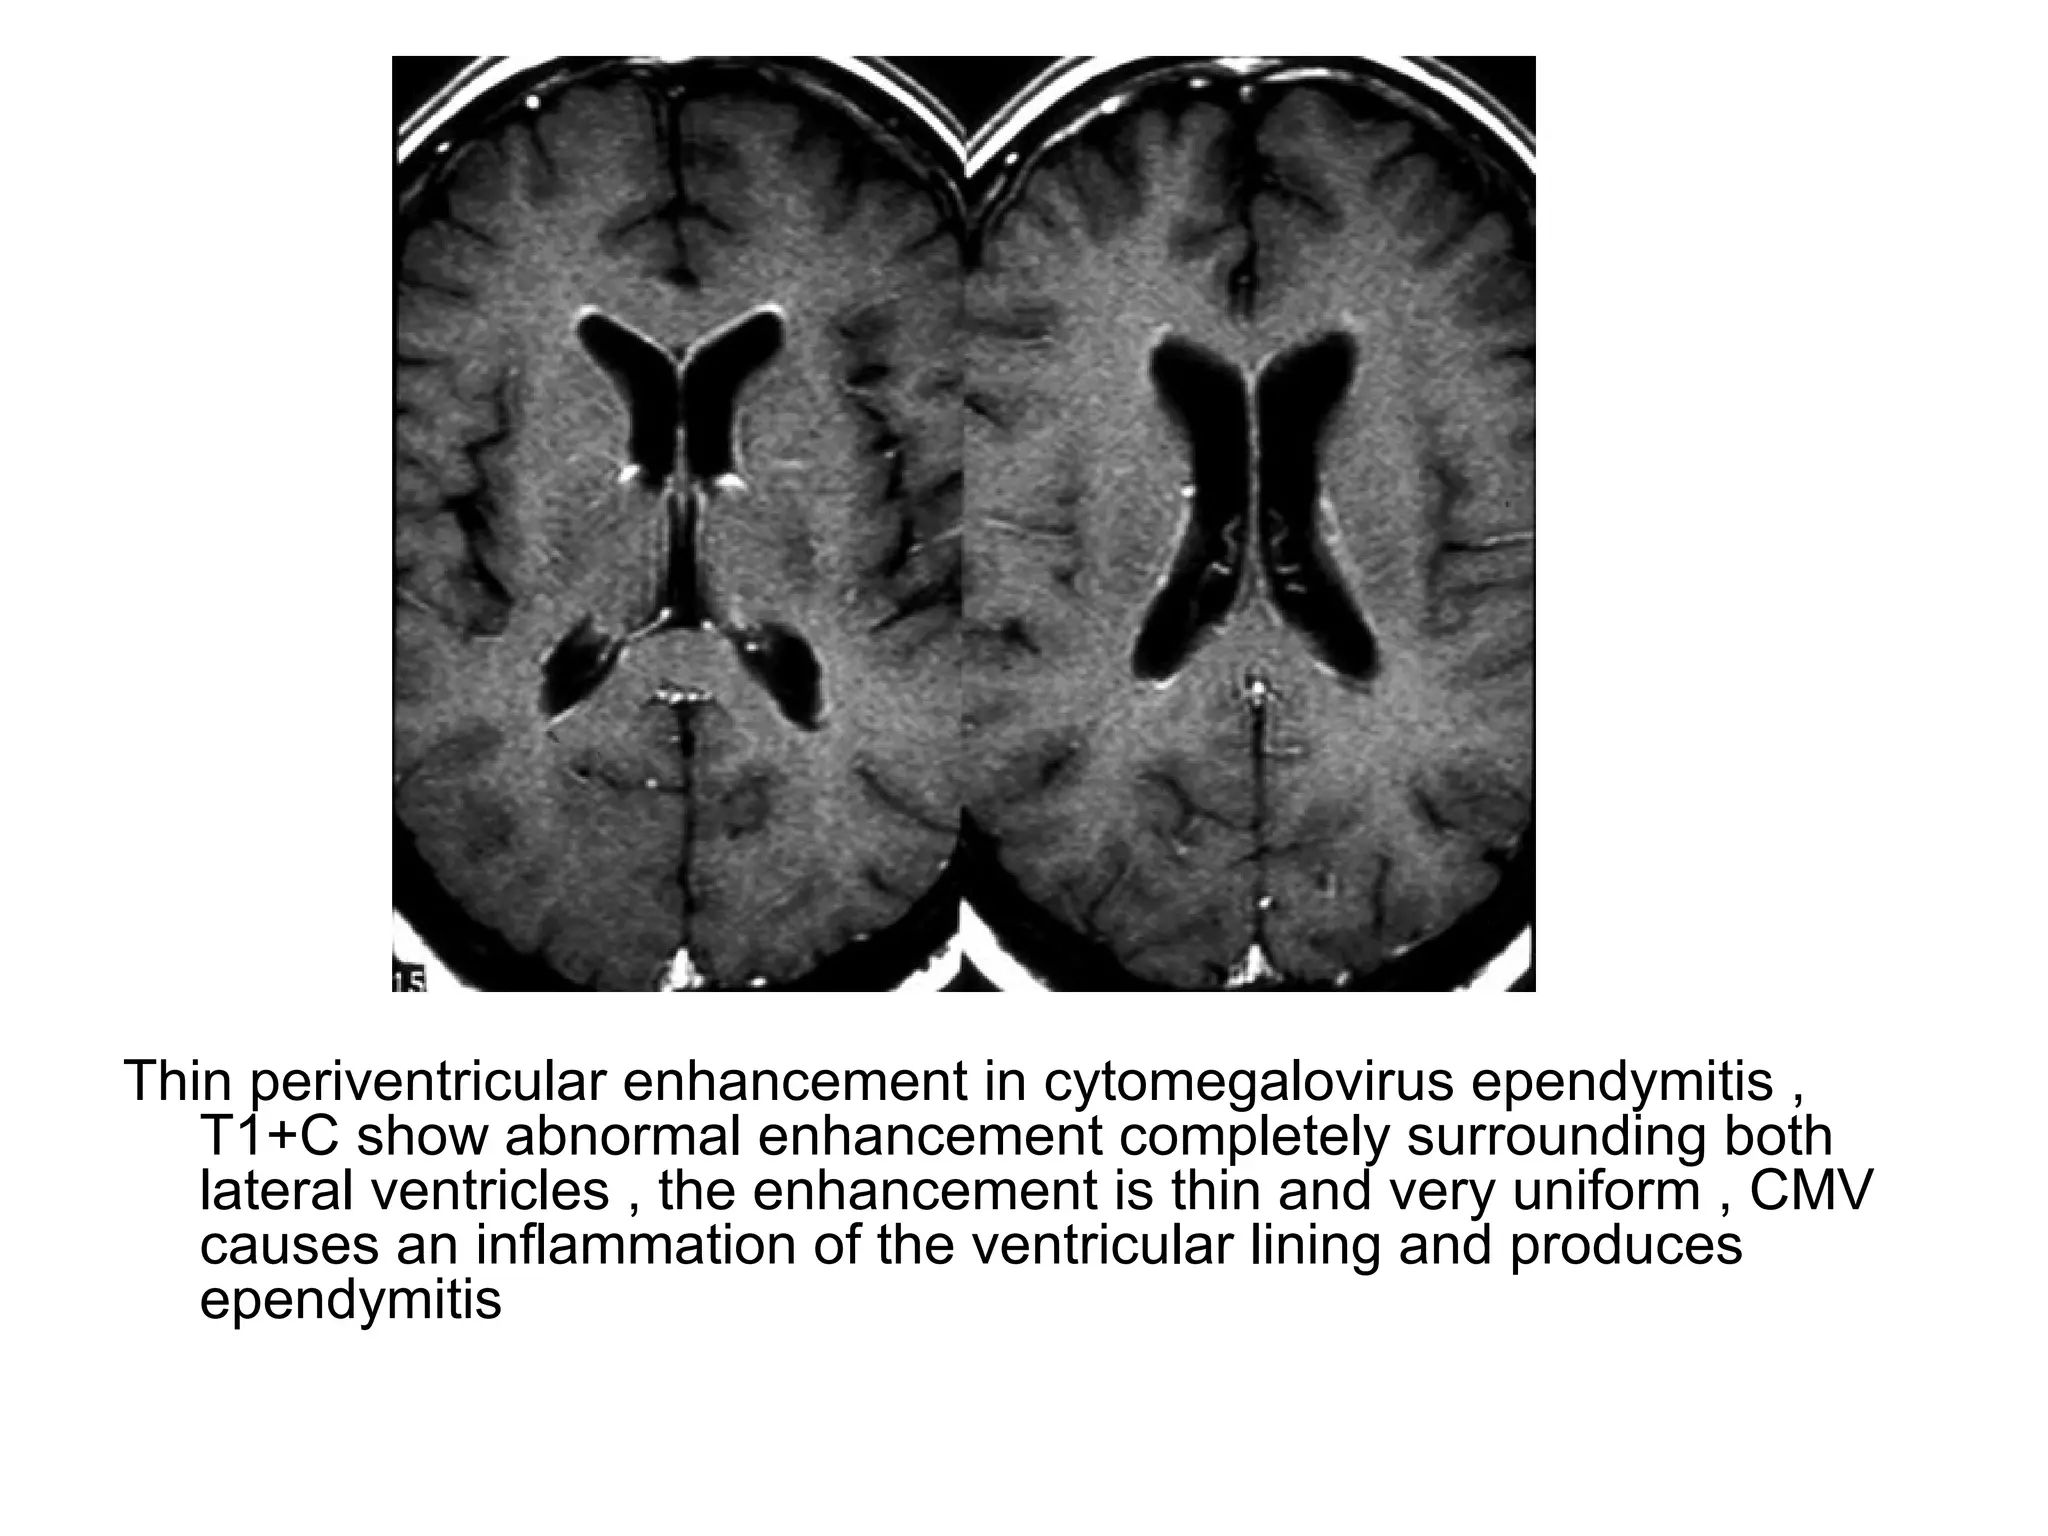

Thin periventricular enhancement in cytomegalovirus ependymitis ,

T1+C show abnormal enhancement completely surrounding both

lateral ventricles , the enhancement is thin and very uniform , CMV

causes an inflammation of the ventricular lining and produces

ependymitis